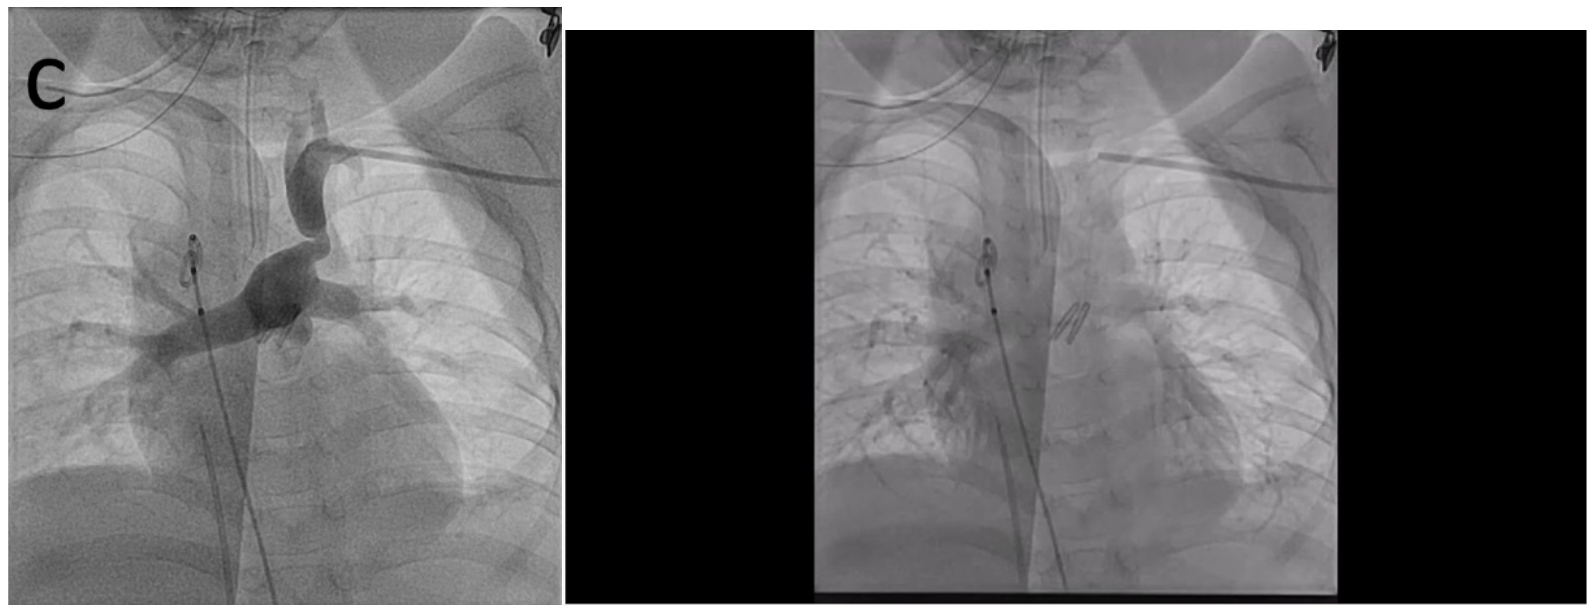

Aortic angiography showed a right aortic arch with only right carotid and right subclavian arteries and retrograde filling of the left carotid, left subclavian artery, and pulmonary arteries (Figure A/B, Video 1). Angiography of the left subclavian artery showed the tortuous, stenotic arterial connection between the pulmonary arteries and left subclavian artery (Figure C, Video 2). After stent placement, there was marked improvement in the caliber of the vessel and systemic saturations (Figure 1D, Video 3). Cerebral NIRS monitoring was used during the procedure with no change after stent placement. She has maintained reasonable saturations and has been seizure-free for over 3 years without neurologic deterioration or further cardiac intervention.